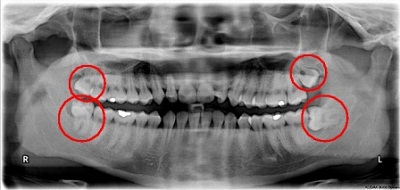

Nhờ sự giới thiệu của bạn bè anh đến nha khoa Dentel kiểm tra. Tại đây, bác sĩ phát hiện chiếc răng khôn mọc lệch đâm vào răng bên cạnh gây tình trạng viêm nhiễm vùng lợi xung quanh. Một tuần sau khi được can thiệp bằng phương pháp nhổ răng không không đau tại Dentel anh đã thoát khỏi những cơn đau.

BS Phạm Việt Hùng cho biết: “Răng khôn là răng nằm phía trong cùng của hai hàm răng ở người trưởng thành. Loại răng này mọc ở người từ 17 đến 25 tuổi. Hàm răng của con người thường chỉ đủ chỗ cho 28 răng (14 răng hàm trên và 14 răng hàm dưới) nhưng trên thực tế mỗi người có tới 32 răng vì mọc thêm 4 răng không ở hai hàm. Chính vì không đủ chỗ để mọc một cách bình thường nên những chiếc răng khôn thường “tự tìm đường khác” như mọc ngược về phía xương hoặc đâm thẳng về phía chiếc răng hàm đứng kế bên.”

Triệu chứng sớm của việc răng khôn mọc lệch thường là những cơn đau âm ỉ. Khi răng khôn mọc đâm sang răng bên cạnh, nó sẽ làm “chiếc răng khỏe mạnh” dần bị tiêu hủy, lung lay có thể dẫn đến sâu, nặng hơn nó sẽ khiến chiếc răng này bị xô đẩy chèn ép và rụng đi.